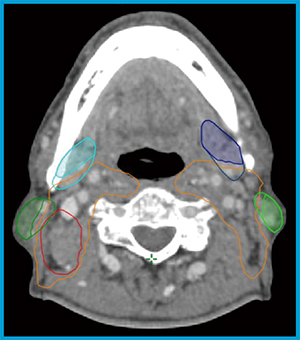

筆者は,最適化を実行する際に,明確な命令を設定することが重要と考えている。例えば,標的と危険臓器がオーバーラップしている場合について,それぞれの輪郭に対して矛盾する最適化(例:標的の最低線量が危険臓器の最大線量を上回るような最適化)を行えば,理想の分布を得ることは難しい。その場合には,図1のように標的や危険臓器の輪郭を分割し,各領域に対して矛盾のないobjectを設定することで,明確な命令を設定することができる。その際に,1〜2mm程度のマージンを取ることで,互いのobjectが干渉しにくい状況を作ることが,効果的な最適化につながる。

図1 危険臓器の輪郭分割例